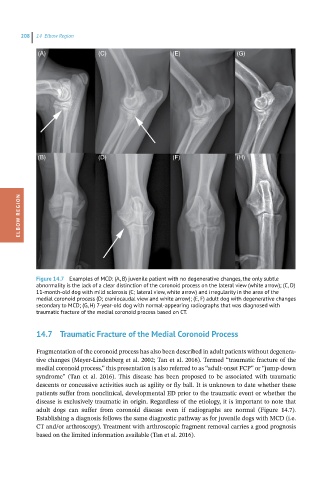

Figure 14.7 Examples of MCD: (A, B) juvenile patient with no degenerative changes, the only subtle

abnormality is the lack of a clear distinction of the coronoid process on the lateral view (white arrow); (C, D)

11-month-old dog with mild sclerosis (C; lateral view, white arrow) and irregularity in the area of the

medial coronoid process (D; craniocaudal view and white arrow); (E, F) adult dog with degenerative changes

secondary to MCD; (G, H) 7-year-old dog with normal-appearing radiographs that was diagnosed with

traumatic fracture of the medial coronoid process based on CT.

adult dogs can suffer from coronoid disease even if radiographs are normal (Figure 14.7).